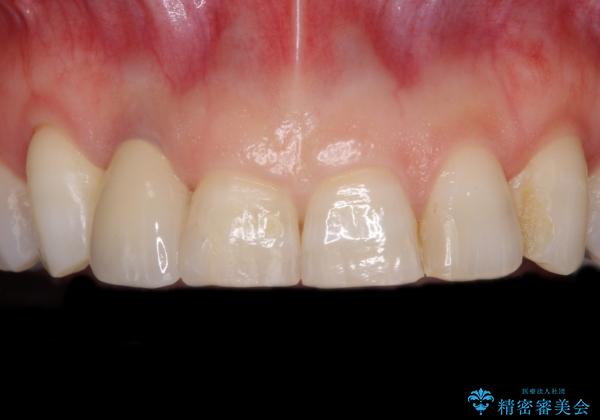

仮歯に置き換えた際に歯周外科処置を行い、歯肉の腫脹が落ち着いたことを確認してオールセラミッククラウンにて補綴することとしました。

外科処置後の痛みを気にしていましたが、小規模の処置であったため、痛みを感じることはほとんどありませんでした。

気になっていた腫脹がなくなり、患者様には大変満足していただきました。